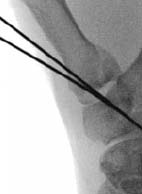

中手骨頸部骨折はよく見られ、典型的には第4指中手骨と第5指中手骨に生じます。「ボクサー骨折」と呼ばれることが多いこの骨折は、乱闘や硬い物体を殴打した際に発生します。中手骨頸部骨折で特に注意することは骨の回旋です。骨が回旋すると、指を曲げた時に隣の指と重なる現象が生じます。頸部の背側への衝撃と掌側粉砕、そして中手指節間関節(MCP:指の第3関節)の掌側にある内在筋の牽引により、頂点背側屈曲が生じることがよくあります。整復はJahss法(下図)を用いて行われます。この方法では、指節間関節を屈曲させ、曲げた指に圧力をかけ、頭部を背側に押しながら、中手骨幹部に背側からの反圧を加えます。

文献5】より